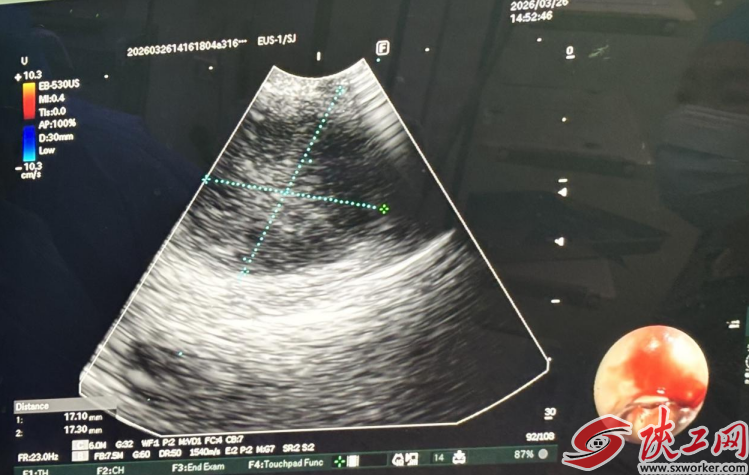

术中,副主任医师谢波将一根特制的、前端搭载微型超声探头的支气管镜伸入患者气道,通过实时超声扫描,屏幕上清晰地显示出气道外、血管旁的肿大淋巴结位置,完美地突破了传统支气管镜的“视觉盲区”。在超声的精确引导下,将一根细小的穿刺针安全地通过支气管壁,分别于右肺中间段支气管近上叶嵴病灶及4R淋巴结行EBUS-TBNA,成功获取了足量的细胞和组织条送病理及细胞学检查。